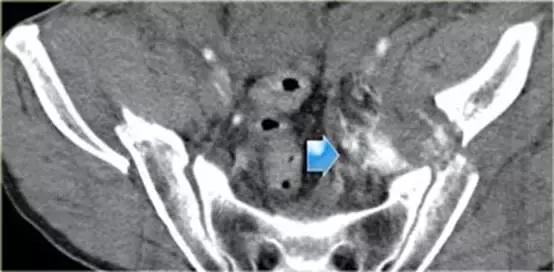

同一病人的CT常规增强检查

结果

有一个指向膀胱的骨盆骨折碎片。

膀胱直肠隐窝积液。

10%骨盆骨折伴有膀胱破裂。

最初认为膀胱破裂都是由骨盆骨折引起,但现在知道只有1/3的膀胱破裂是因为游离碎骨片造成的,另外2/3是由于剪切伤作用于膀胱造成破裂。